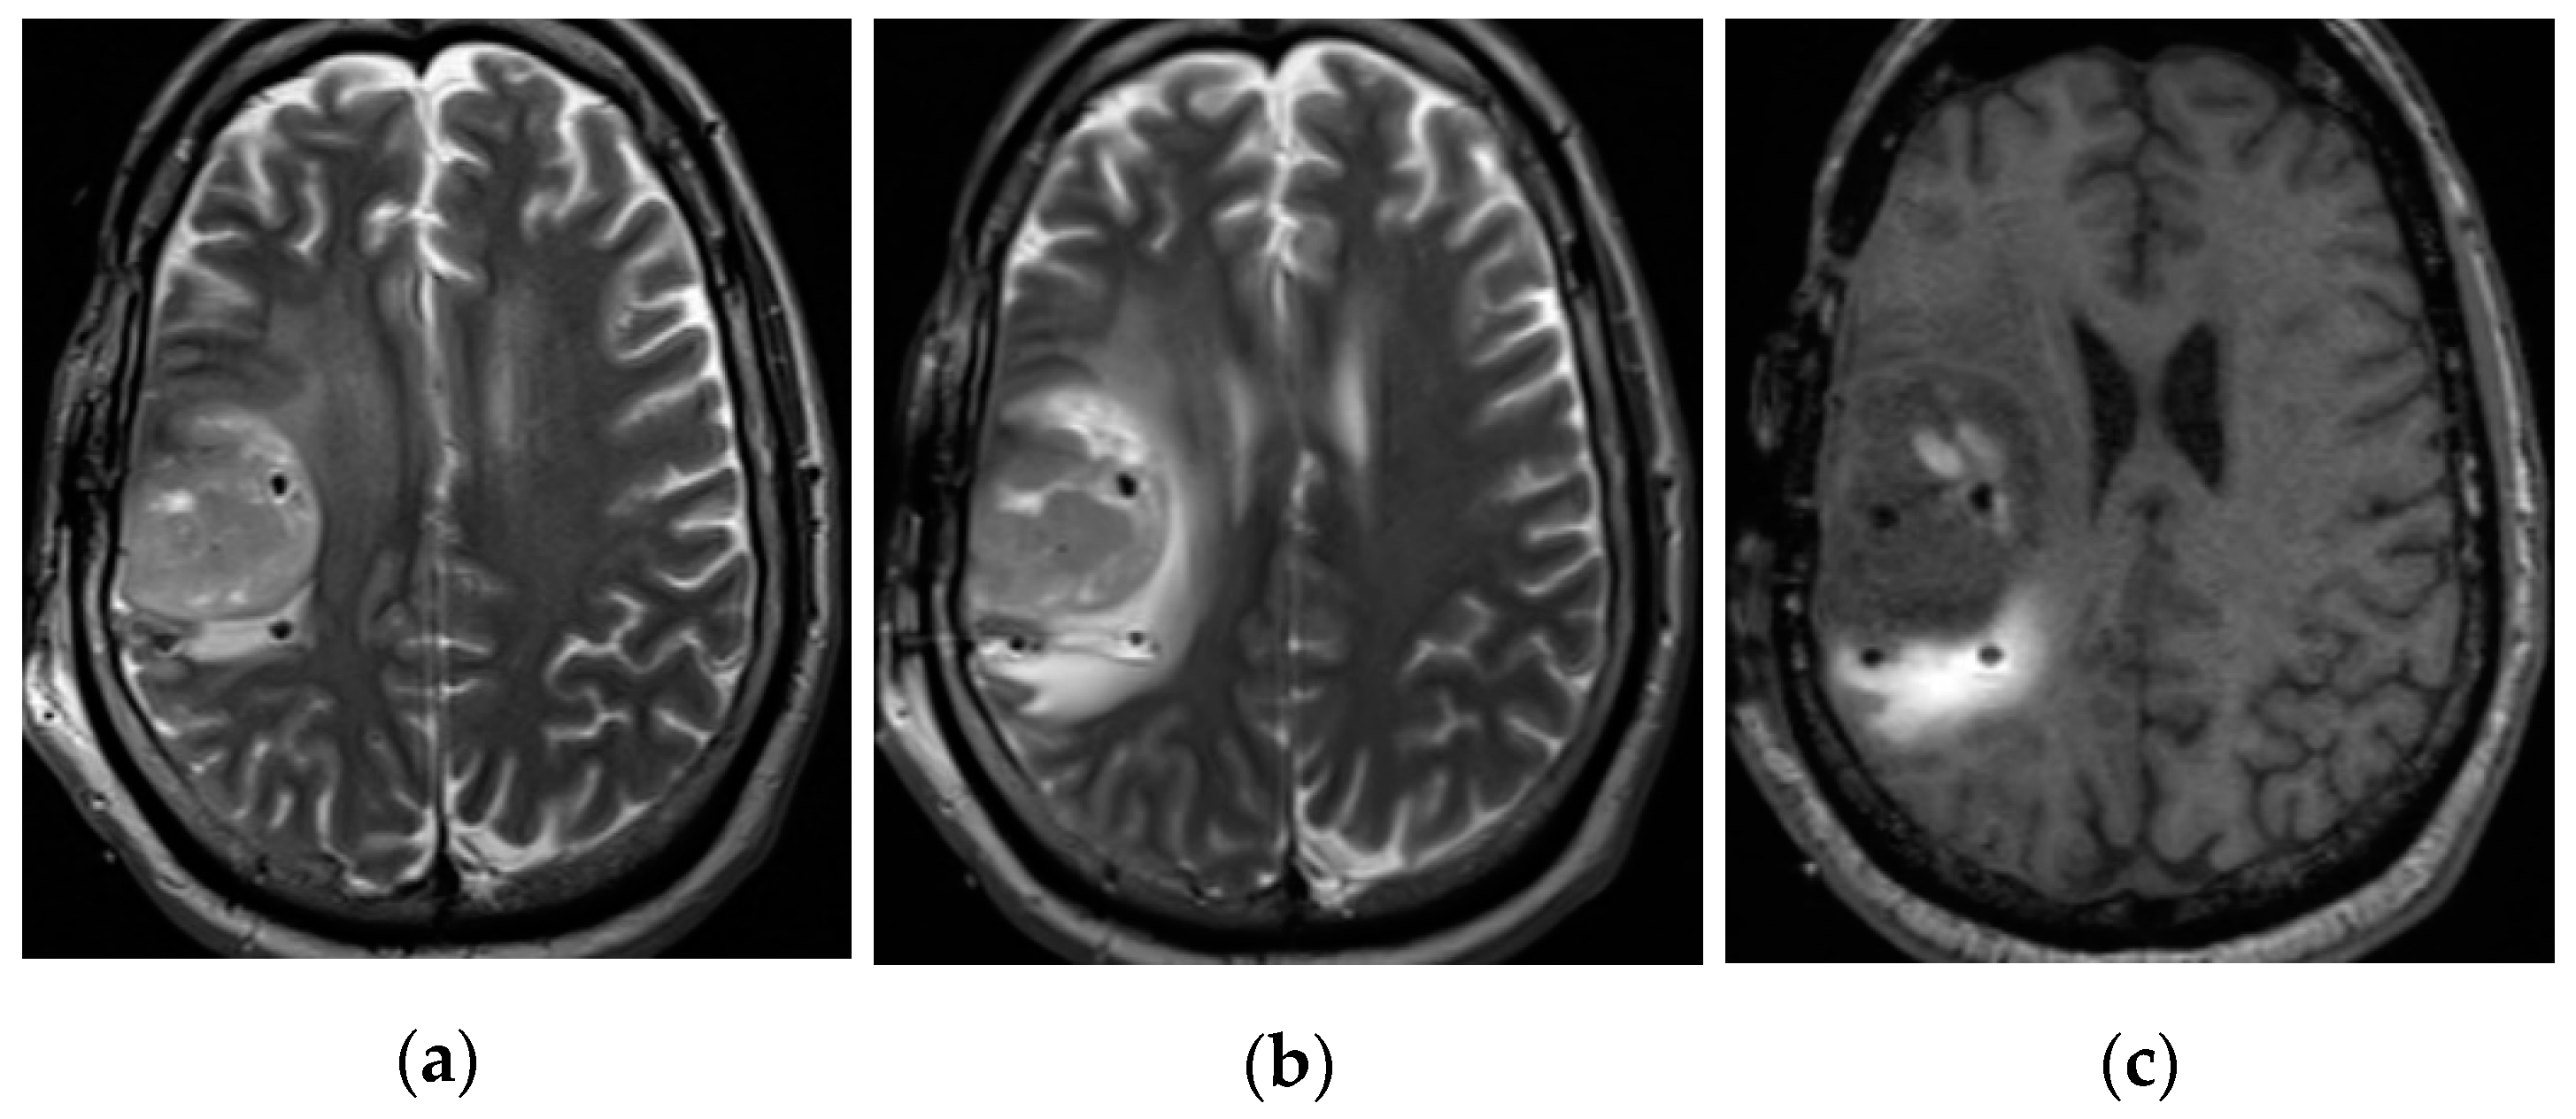

2.2.2. Imaging Protocols

2.2.3. Concentration Measurement

2.2.4. Distribution Volume Measurement